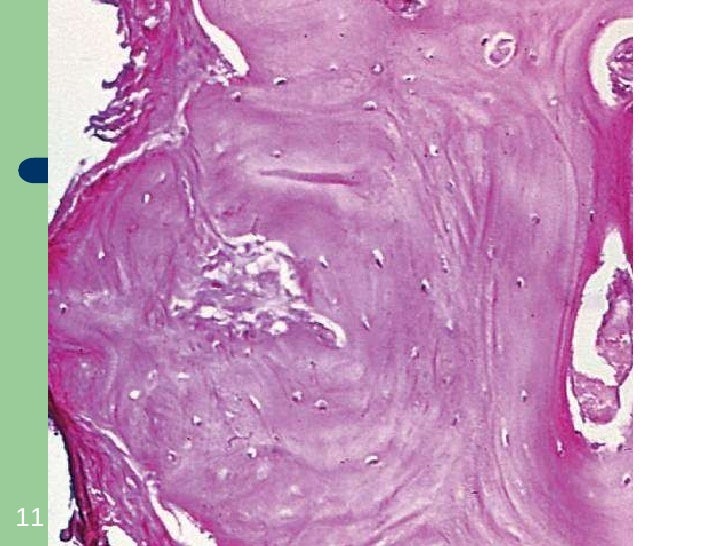

Per osteoma in campo medico, si intende una forma di tumore delle ossa di tipo benigno che si forma più frequentemente nelle ossa del cranio.

- Osteoma osteoide, la forma più conosciuta, esistono poi altre varianti della neoplasia come il fibro-osteoma e il condro-osteoma.